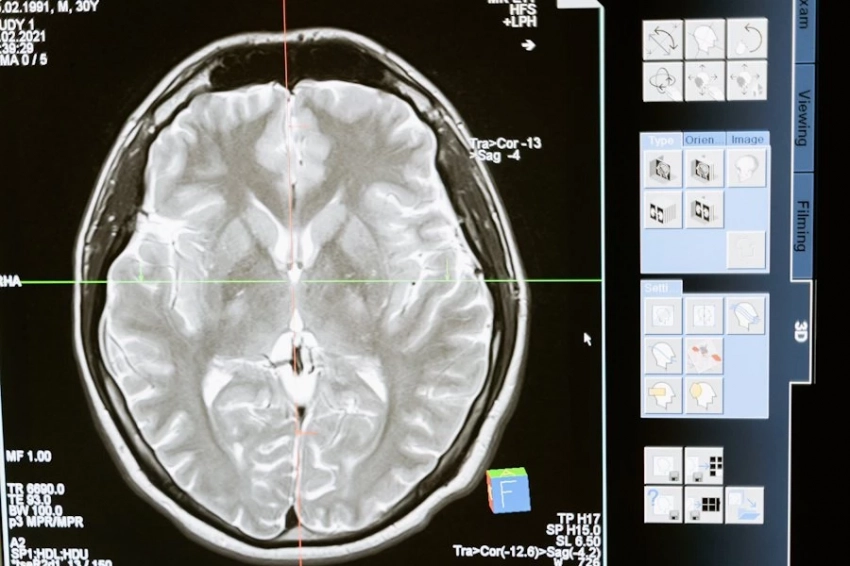

Онколог Воробьев: Потеря обоняния и вкуса могут быть связаны с опухолями головного мозга

Опухоль головного мозга в лобной доле может вызвать потерю обоняния, а также привести к другим симптомам, таким как затруднения с речью, концентрацией внимания или усвоением новой информации. «Опухоль головного мозга в теменной доле может привести к трудностям в обработке информации от органов чувств, включая обоняние и вкус, а также вызвать другие симптомы, вроде затруднений в распознавании лиц или объектов и нарушения координации движений», — добавляет врач.

Опухоль носа, называемая обонятельной нейробластомой, также может повлиять на обоняние. Возможны также кровотечения из носа, слезотечение и другие симптомы.